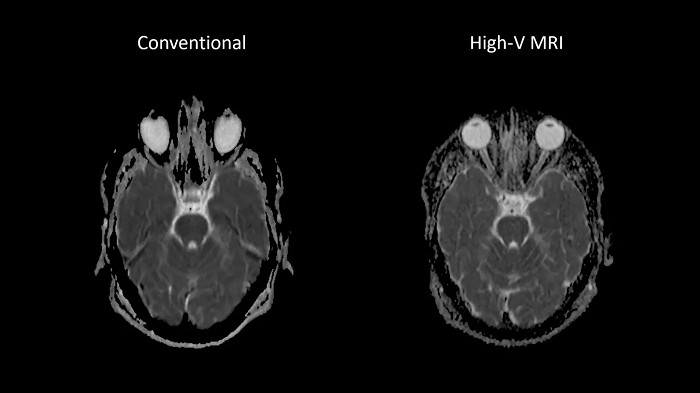

Reduced susceptibility challenges with High-V MRI

In MRI, susceptibility artifacts are a familiar phenomenon.

One notable example of such artifacts is at air-tissue interfaces, as they occur at the sinuses and orbits. The unique field strength of High-V MRI offers physical advantages that reduce susceptibility artifacts. This leads to reduced geometric distortions in diffusion imaging which results in improved diagnostic quality.

80 cm bore MAGNETOM Free.Max

Image Courtesy: University Hospital Erlangen, Germany | Image-ID: 1aaaa3439 | 4aaaa0297